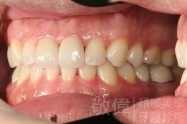

變臉矯正,原來戽斗妹跟大歪臉變成自信正妹

經由本院3D數影X光影像儀分析、與3D齒顎顏矯正技術,再配合口腔顎面正顎專科醫師施以正顎手術治療,雙方共同合作,使患者臉部外觀有很好的改善,大歪變小歪,產生了天南地北的大改變,她的人生也整個變得不一樣。

因為矯正與正顎手術的配合,使「戽斗妹」變成了「陽光正妹」,完全的改變了她的人生,在面對各種場合、與人交際都散發出自信微笑。所以,奉勸家長,如果小朋友有臉顎畸型的問題,應該考慮配合做這種簡單、安全、有效的正顎手術。